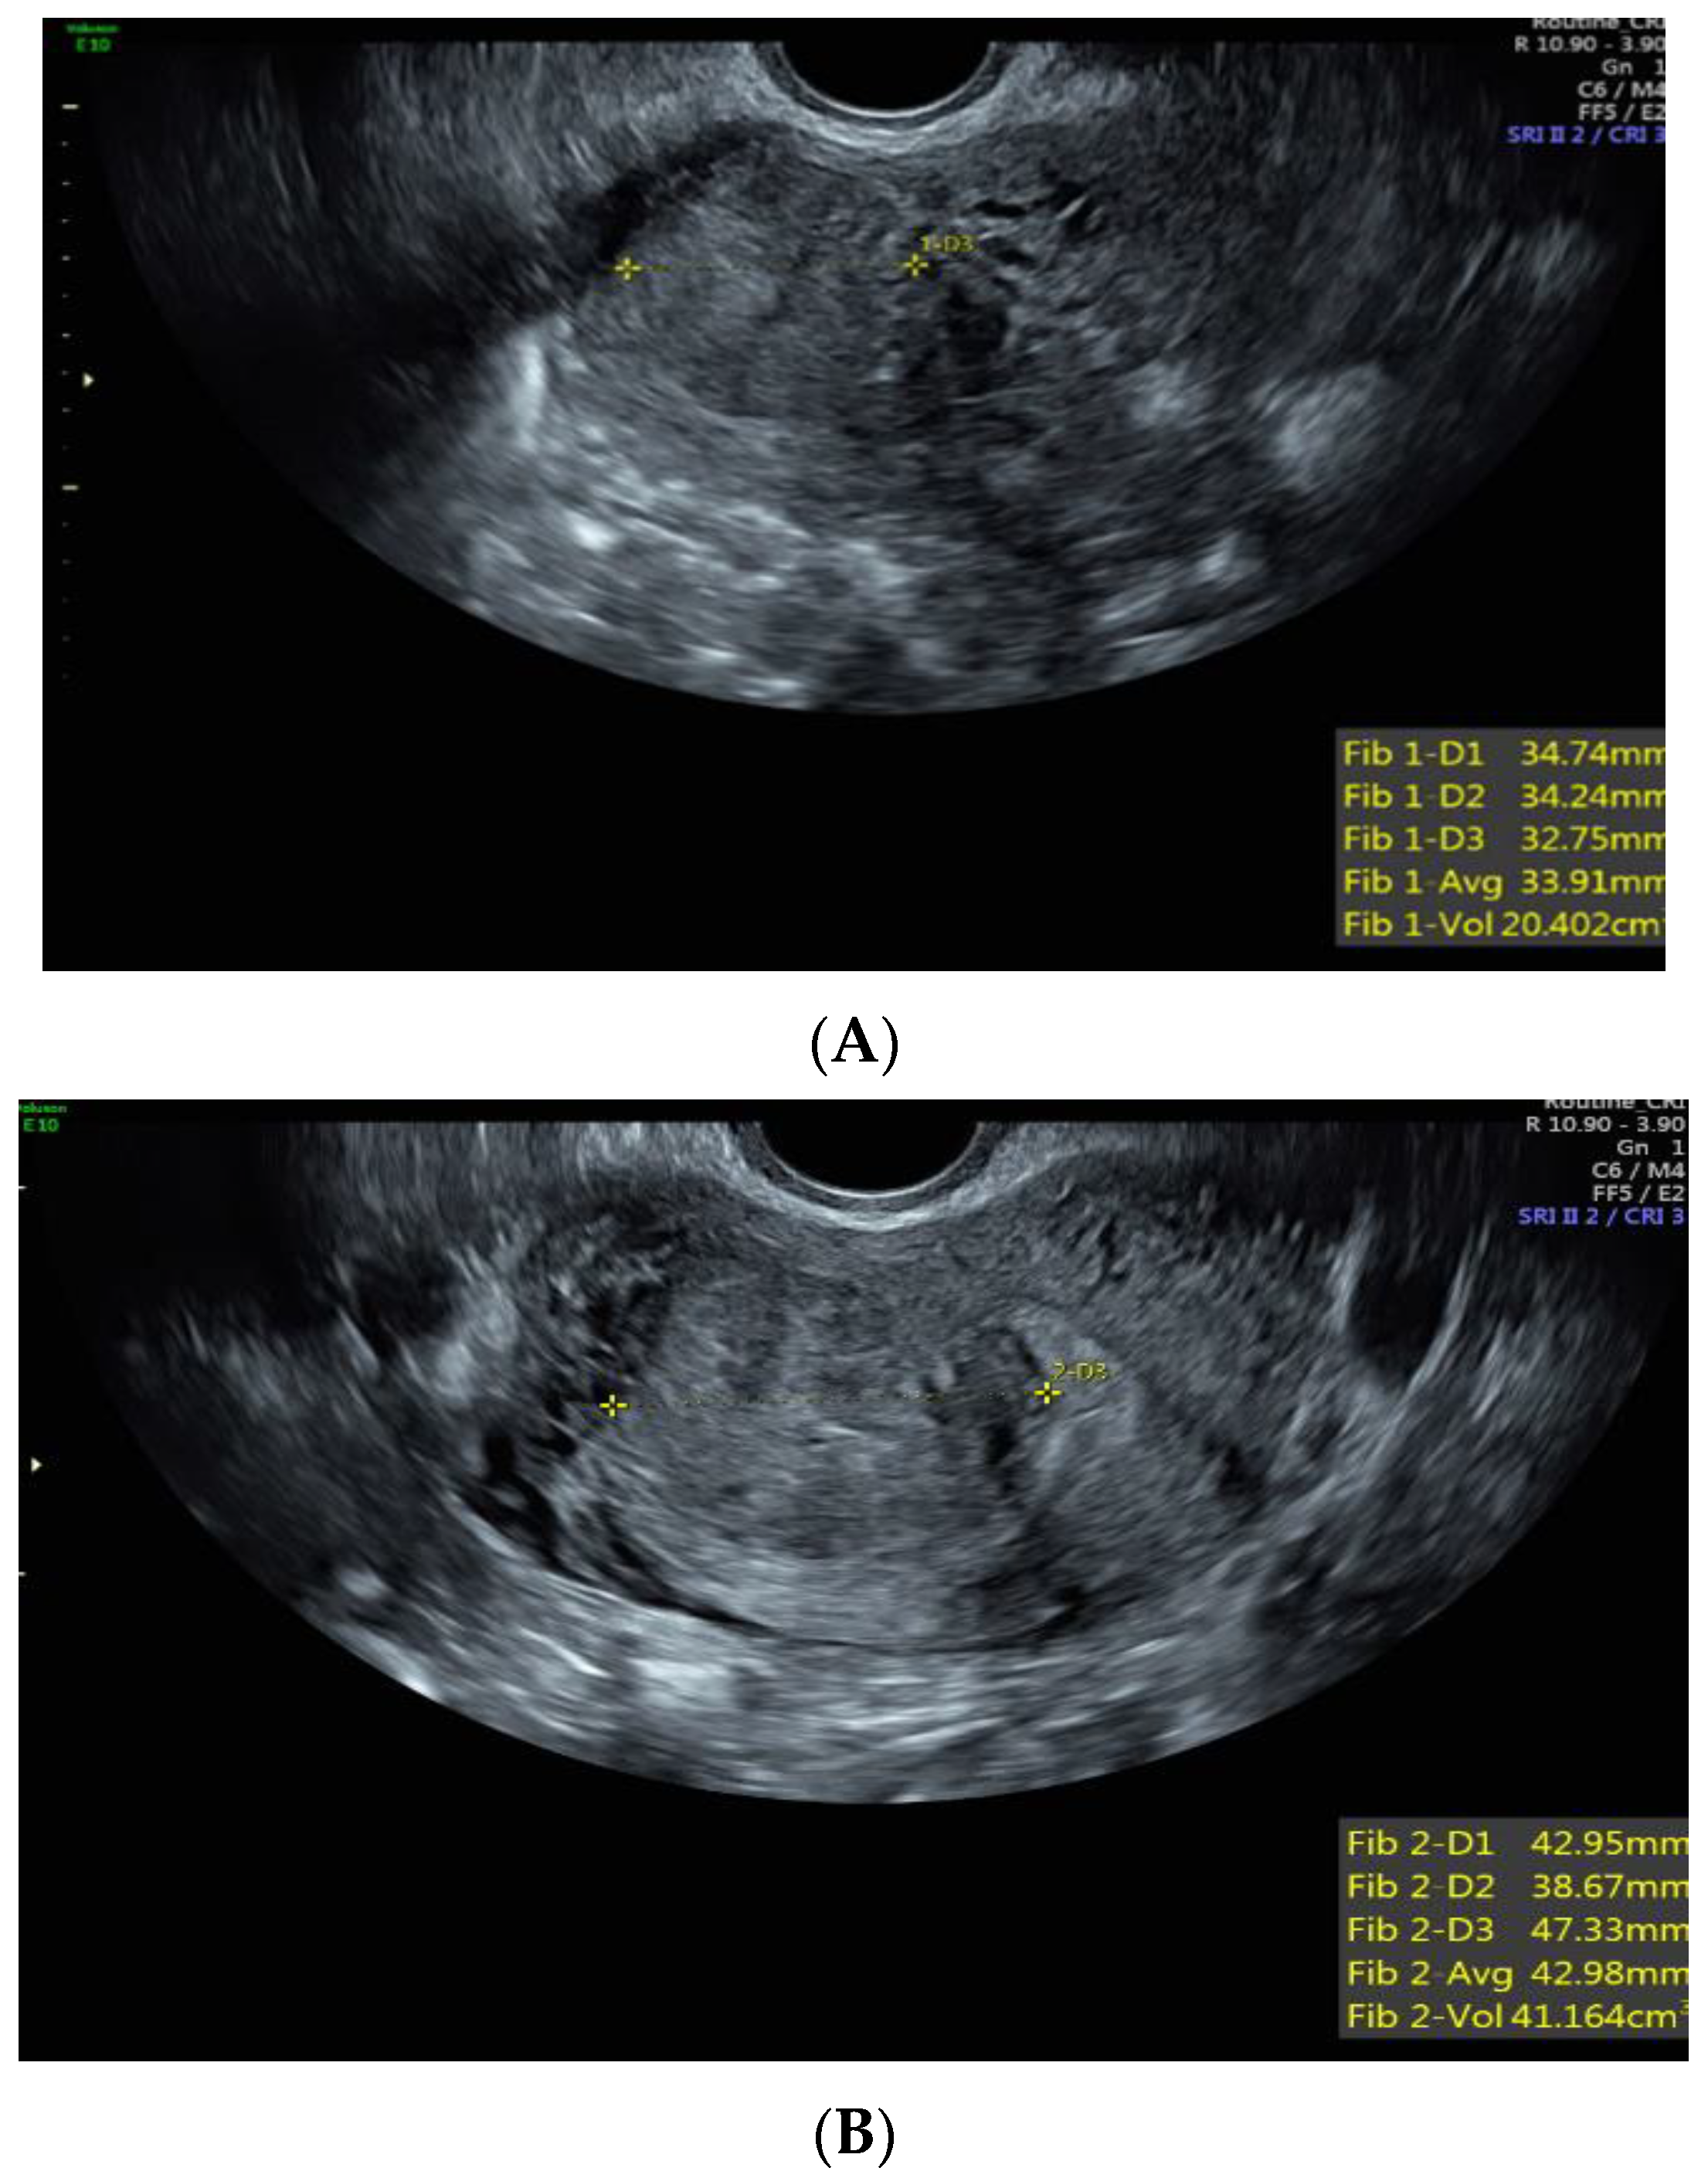

Case 1: A 37-year-old White, non-Hispanic patient presented with heavy menstrual bleeding and pelvic pain. A pelvic ultrasound revealed a 4.5 cm intramural uterine fibroid (Figure 1A) and a 3.5 cm submucosal uterine fibroid (Figure 1B). She underwent a total laparoscopic hysterectomy with bilateral salpingectomy. Pathology confirmed a leiomyoma with features of FH deficiency; germline genetic testing was negative for known pathogenic mutations.

Figure 1. (A) Anterior intramural uterine fibroid. (B) Anterior submucous uterine fibroid.